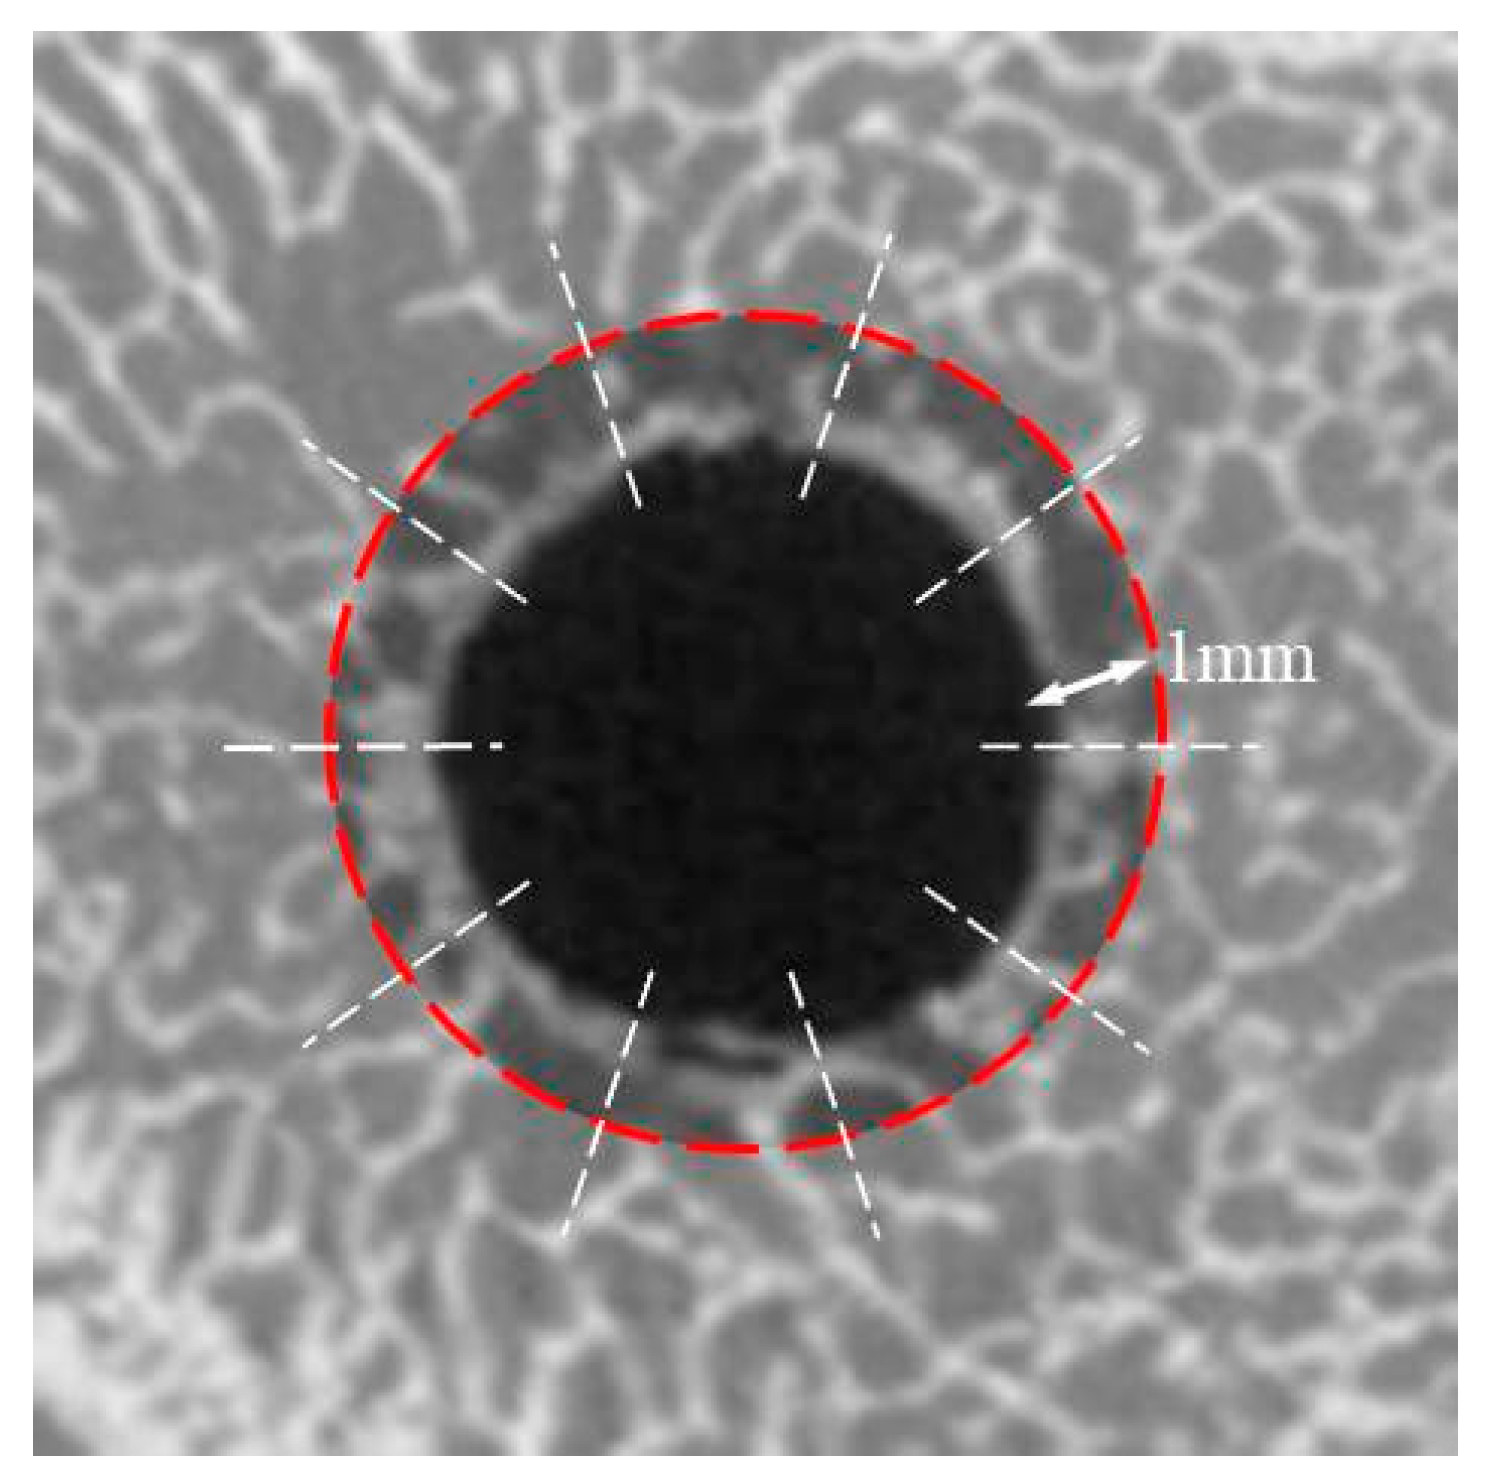

3.2. Bone Density